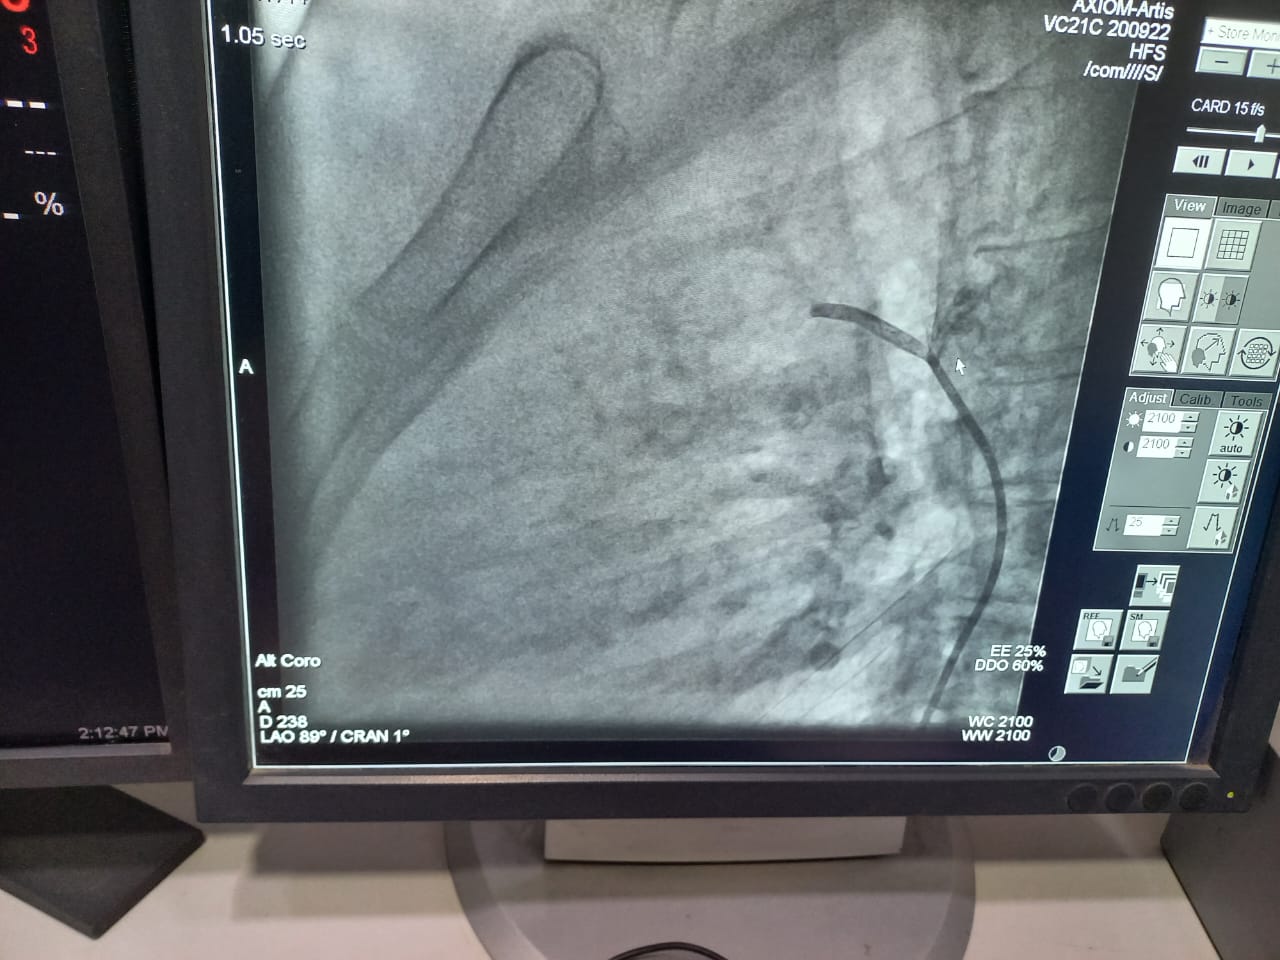

من جانبه أوضح الدكتور محمد النعمانى رئيس قسم القلب و الأوعية الدموية أنه تم عمل غلق وصلة شريانية بين الشريان الرئوي والأورطى لطالبة بإحدى كليات جامعة المنوفية عن طريق القسطرة الداخلية بدلا من جراحة القلب المفتوح والتى تجرى عن طريق تخدير موضعى فقط والمريض واعى ويخرج المريض من المستشفى في اليوم التالى للقسطرة مباشرة. و أضاف النعماني أنها تعد حالة من الحالات الصعبة نظرا لكون الوصلة الشريانية طويلة و يبلغ طولها حوالى ٢٧ مم.